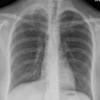

Lymphoma -Mediastinal and left axillary nodes (see CT)

Date: 04/01/2014

Views: 2580